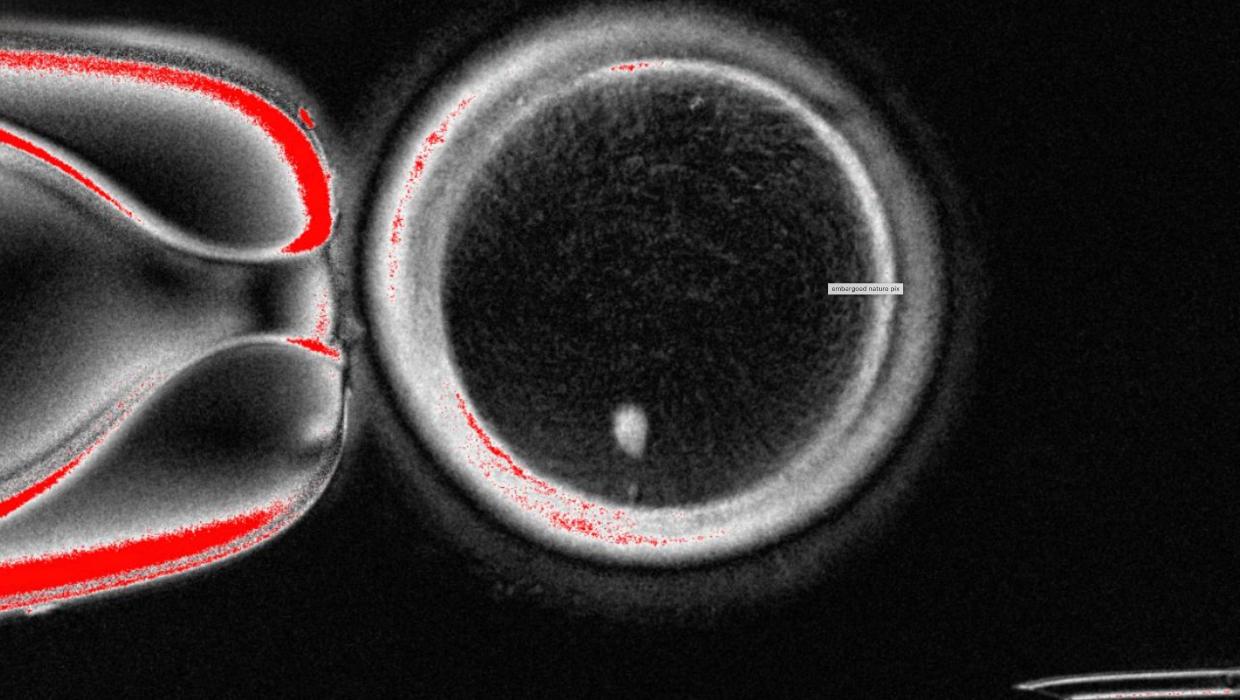

Groundbreaking research from US scientists has achieved a significant milestone in reproductive biology by transforming human skin cells into fertilizable human eggs. This innovative approach could pave the way for developing lab-grown eggs and sperm, potentially aiding individuals struggling with infertility.

The study, published in a leading scientific journal, highlights the potential of using skin cells to create gametes. By reprogramming these cells, researchers aim to produce viable eggs that can be fertilized, offering hope to those facing challenges in natural conception.

According to a team at the Massachusetts Institute of Technology (MIT), the successful conversion of skin cells into eggs marks a substantial advancement in reproductive technology. The process involves intricate cellular reprogramming techniques that allow researchers to manipulate the genetic material within skin cells, effectively generating the necessary components for egg formation.